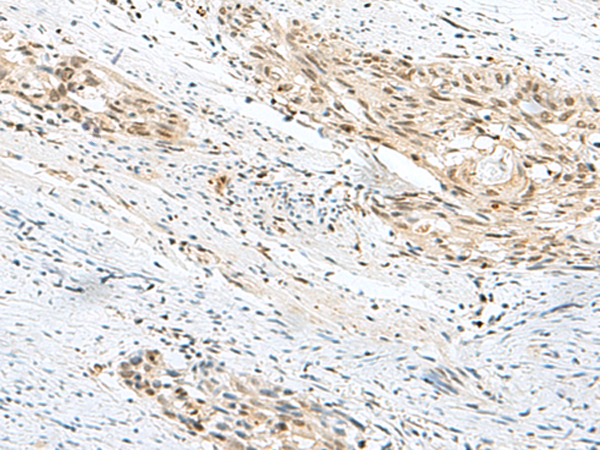

分类: 科研抗体货号: P13550别名: GSG2应用: IHC反应种属: Human